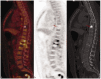

This case report describes a rare giant bone island combined with hemangioma diagnosed in a patient with osteolytic vertebral metastases. The bone island's greatest diameter was 3.15 cm, and bone islands of this size are rare in the literature. This article aims to provide clinicians with information about the diagnosis and relevant literature of bone islands.